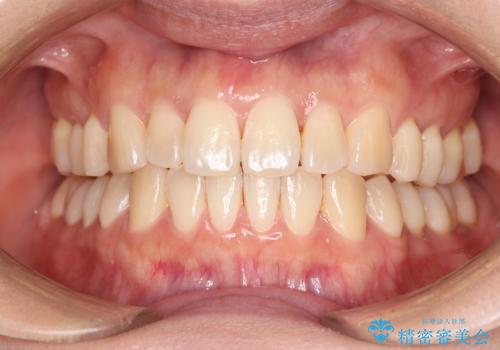

[ セラミック治療 ] 前歯の見た目を改善したい

![[ セラミック治療 ] 前歯の見た目を改善したいの症例 治療前](https://seimitsushinbi.jp/wp/wp-content/uploads/2025/10/IMG_9990-2-500x350.jpg?v=1761816440)

![[ セラミック治療 ] 前歯の見た目を改善したいの症例 治療後](https://seimitsushinbi.jp/wp/wp-content/uploads/2025/10/IMG_9934-500x350.jpg?v=1761816431)